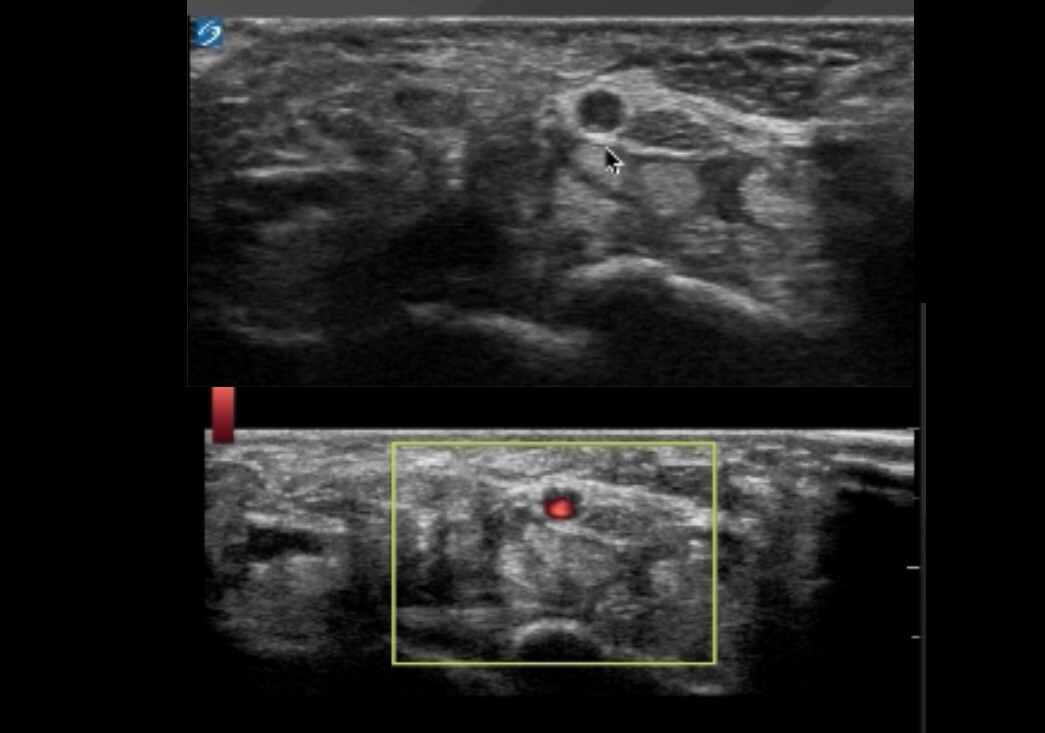

Wrist Carpal Tunnel Differential Diagnosis Image